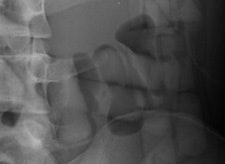

Capsules holding cocaine are of different densities. It is important to perform window-level adjustments to detect drug containers, according to the authors. It also helps for a radiologist to know what the typical size and appearance are of different cocaine containers. With this knowledge, they can be better distinguished from normal intestinal gas, calcifications, scybala, and other foreign bodies.

The authors noted that it was also important for a radiology report to contain a precise description of the number of drug containers that are identified, and to indicate where they are located in the intestinal tract. This makes the job of the feces evaluators easier.